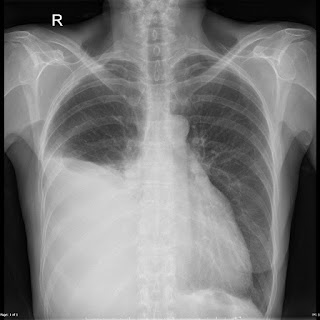

Bệnh nhân chụp X quang ở tư thế đứng:

-Nếu lượng dịch < 100ml: không thấy bất thường trên phim thẳng lẫn phim nghiêng.

-Nếu lượng dịch từ 100-250ml: thường chỉ thấy mờ góc sườn hoành phía sau trên phim nghiêng.

-Nếu lượng dịch từ 250-500ml: thấy được mờ góc sườn hoành bên ngoài trên phim thẳng (tùy theo kích thước của bệnh nhân).

-Nếu hình ảnh xquang mờ 1/3 dưới phổi, lượng dịch khoảng 1l-1,5l, có đường cong damoiseau, nếu dịch còn chảy tự do.

-Nếu xquang mờ nửa dưới phổi: lượng dịch khoảng 2 lít

-Nếu hình ảnh x quang mờ toàn bộ một bên phổi: lượng dịch khoảng 3,5-5 lít